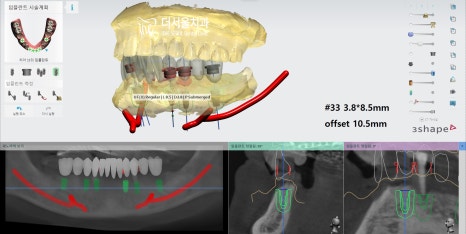

『컴퓨터 분석으로 정확한 식립』

앞서 말했듯이 치조골 소실이 심했기 때문에

GBR이 필요한 곳들이 있었습니다.

위와 같은 세부 계획들을 토대로

본격적인 수술 과정으로 돌입했습니다.

남아있는 잔존치를 발치했습니다.

골이식을 동반한

하악 디지털 임플란트 식립을 진행했습니다.

골이식을 통해 모자란 곳을 보강해 준 다음

계산된 위치에 픽스처를 심어드렸습니다.

잇몸 형성을 도울 힐링 어버트먼트를 결합하고

골융합도를 기다린 후 최종 보철까지 올려드렸습니다.